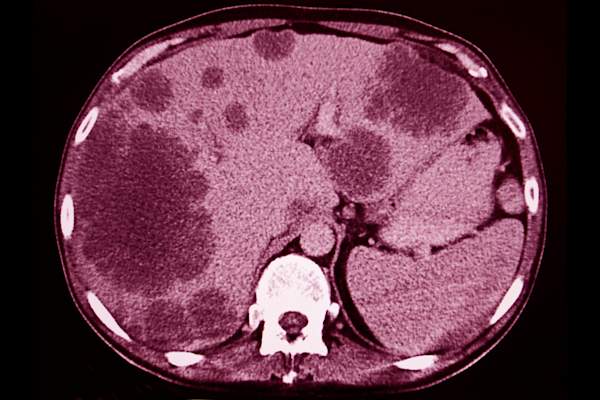

肝转移可能不会引起症状

你可能不是第一个注意到的乳腺癌扩散到肝脏;根据breastcancer.org的说法,通常情况下,没有任何迹象。

肝功能测试可以检测血液中酶和蛋白质的异常水平,这可能表明癌症已经扩散到肝脏。

肝转移的迹象

当肝转移确实引起症状时,可能包括:

- 腹痛或不适;恶心想吐

- 极度疲劳;弱点

- 减肥;缺乏兴趣

- 发热

- 腹胀

- 腿、脚和手的肿胀

- 皮肤或眼白发黄

- 皮肤发痒或起疹子